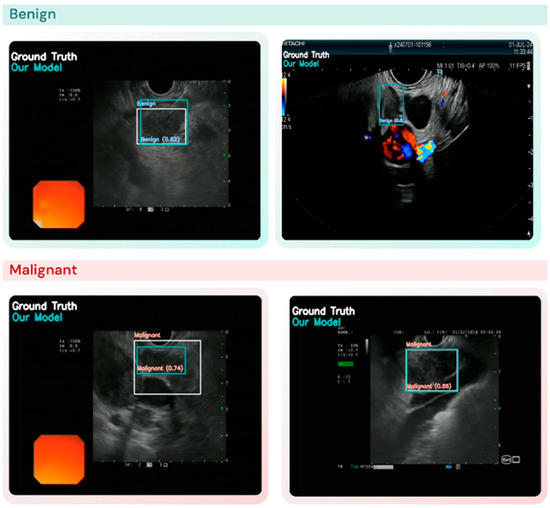

在完成模型训练后,我们采用测试集对其性能进行了系统评估。检测与分类任务分别基于单图像和单病灶进行独立分析,通过系统评估交并比与置信度阈值的25种组合,全面考察模型在不同操作条件下的表现谱系。当模型生成的边界框能够准确包含图像中的淋巴结时,该淋巴结即被正确检测到(图2)。模型整体性能评估包括对良恶性病灶检测与分类结果的比较分析。

图 2. YOLO 模型预测与淋巴结 (LN) 检测和区分的真实情况的比较。